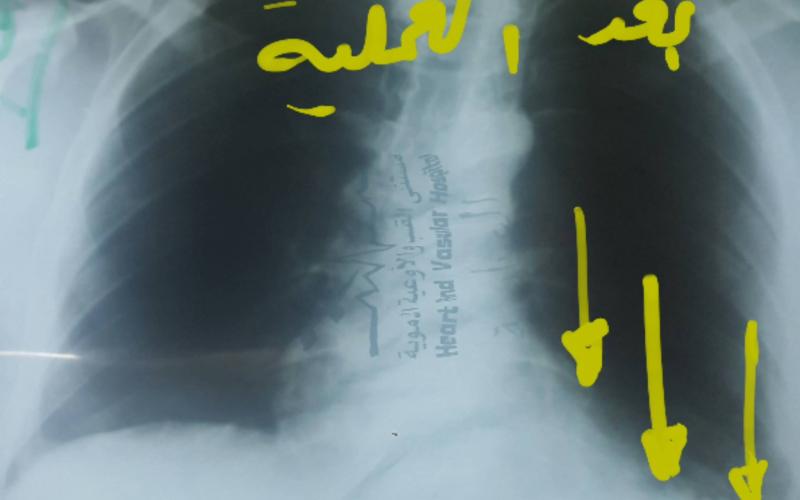

بالصور: إجراء عملية جراحية نوعية بمستشفى الخدمة العامة

غزة - فلسطين الآن

من جديد نجح الفريق الطبي بمستشفى الخدمة العامة برئاسة د. رائد العريني استشاري مناظير وجراحة الصدر والتشوهات الخلقية الصدرية والروبوت الجراحي وزراعة الرئة. و مساعده د.طارق شراب أخصائي الجراحة العامة وفريق العمليات بالمستشفى من إجراء عملية نوعية جديدة للمريض ز .ح البالغ من العمر 25 عام والذي يعاني من ضيق في التنفس منذ سنوات .

وأوضح د رائد العريني أن المريض يعاني منذ سنوات من ضيف في التنفس وحضر إلى المستشفى وقد أجري له الفحص الطبي الإكلينيكي والصور الإشعاعية والمقطعية حيث تبين وجود ارتخاء شديد لعضلة الحجاب الحاجز الأيسر مما يتسبب بصعود الحجاب الحاجز وأحشاء البطن من معدة وقولون والطحال إلى تجويف الصدر مانعا لتمدد الرئة اليسرى وصعوبة في التنفس.

والجدير ذكره أن د. العريني أجرى خلال الشهر الجاري عملية لمريض آخر يعاني من نفس المشكلة حيث لاقت نجاحا باهرا بحيث تحسنت حالة المريض بشكل كبير بعد إجراء العملية.

وأكد العريني أن المريض غادر المستشفى بصحة جيدة بعد مكوثه 3 أيام نقاهة، شاكرا الجهود المبذولة.